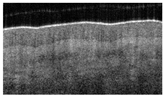

Glabrous skin has a thicker epidermis and sweat glands with visible ducts. The characteristic skin lines are visualized (Figure 2a,b) from the en-face perspective. The skin covering the dorsum of the hand has a thinner epidermal band. Skin thickness varies in different areas of the body and with age (Figure 2).

Figure 2.

OCT of glabrous skin at different depths: (a) 0.3 mm, (b) 0.6 mm, (c) superficial burn 0.3 mm, and (d) deep burn.

Skin lines are a characteristic feature of the glabrous skin of the palms and the soles (Figure 2). OCT detected skin lines in burn wounds from the en-face perspective, even when the lines were clinically invisible. Skin lines can be visualized in the dermis at depth (Figure 2a,b). We observed that grafting became necessary when the skin lines disappeared, indicating a deep dermal injury. (Figure 2d). More importantly, persistent lines (Figure 2c) were associated with spontaneous healing and may thus represent a favorable outcome marker. In superficial palm burns, the skin lines become blurred at the 0.3 mm level (Figure 3c) and disappear completely in deep burns (Figure 2d).